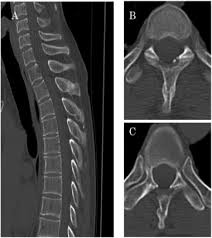

Thoracic transverse process fractures (ttpfs) are injuries that go unnoticed during traditional autopsies, as demonstrated by a lack of ct scans showed transverse process fractures in 39 (7.3%) patients.

A transverse process fracture at the level of l5 is a surrogate marker of vertical instability of the pelvic fracture due to the attachment of the iliolumbar ligaments. Possible causes, signs and symptoms, standard treatment options and means of care and support. Transverse processes are used as lever arms by the deep spinal muscles to maintain posture and to induce rotation and lateral bending. It may occur as an avulsion fracture due to strong contracture of the muscles. Although the fracture is not associated with spinal cord damage and neurological deficits, the extreme force of the injury can cause visceral injuries and internal hemorrhage. The presence of other injuries might also be assessed due to the level of force needed to break the transverse process. In 78% of transverse process fractures, ct scanning showed that the fracture extended into the transverse foramen. Transverse process fractures caused by stress are likely under detected since even an acute transverse process fracture requires a high index of suspicion to be correctly identified(4,7). Here is an example of a patient with a benign looking transverse process fracture with an associated significant injury to the back. Transverse process fracture you have fractured a transverse process. Thoracic transverse process fractures (ttpfs) are injuries that go unnoticed during traditional autopsies, as demonstrated by a lack of medicolegal publications regarding ttpfs. We retrospectively reviewed the reports of lumbar spine and abdominopelvic ct scans from 2017 and 2018 to classify the types of spine fractures, their mechanism of injury, treatment and. Up to 60% of lumbar transverse process fractures identified on ct will be missed on plain radiographs.

Fractures Of The Thoracic And Lumbar Spine Orthoinfo Aaos from orthoinfo.aaos.org There is one on both sides of every vertebra in the… a transverse process fracture is quite a rare injury. A transverse process fracture is a break in 1 or more transverse process. Transverse process fracture is a rare and stable fracture of the spine. We retrospectively reviewed the reports of lumbar spine and abdominopelvic ct scans from 2017 and 2018 to classify the types of spine fractures, their mechanism of injury, treatment and. This may be done through diet and exercise. Transverse process fractures caused by stress are likely under detected since even an acute transverse process fracture requires a high index of suspicion to be correctly identified(4,7). Thoracic transverse process fractures (ttpfs) are injuries that go unnoticed during traditional autopsies, as demonstrated by a lack of medicolegal publications regarding ttpfs. Transverse processes are typically fractured in direct blows from athletics touch or impact from falls from bikes/motorbikes or by heights.

However, postmortem computed tomography (pmct) has made detection of this type of injury easy. There are two transverse processes that extend off each vertebra in the details: What is a transverse process fracture? It may occur as an avulsion fracture due to strong contracture of the muscles. It occurs as a result of sudden and extreme trauma. If ct confirms isolated injury lateral flexion/extension views are indicated to rule out dynamic instability. Vertebral angiography, performed in eight patients with fractures involving the transverse foramen, showed dissection or occlusion of the vertebral artery in seven (88%) instances. This part extends out from the side of the main body of the bone (called the vertebral body). A transverse process fracture at the level of l5 is a surrogate marker of vertical instability of the pelvic fracture due to the attachment of the iliolumbar ligaments. We retrospectively reviewed the reports of lumbar spine and abdominopelvic ct scans from 2017 and 2018 to classify the types of spine fractures, their mechanism of injury, treatment and. Up to 60% of lumbar transverse process fractures identified on ct will be missed on plain radiographs. In 78% of transverse process fractures, ct scanning showed that the fracture extended into the transverse foramen. Transverse process fractures identified on helical computed tomography (ct) scans without the presence of any other fracture or.